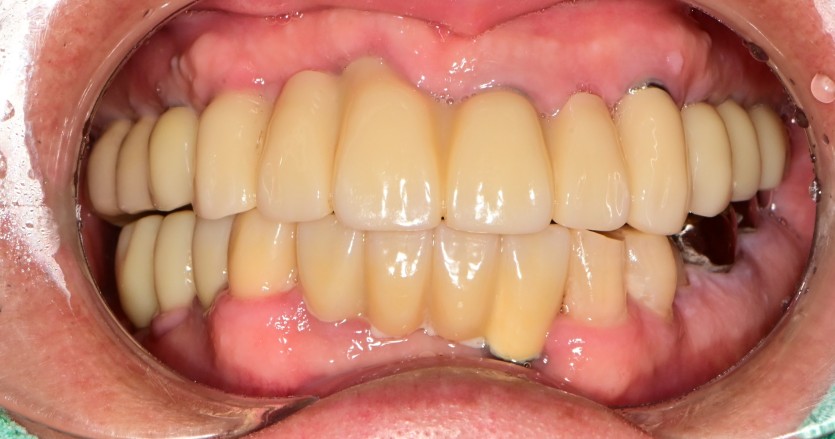

전체 임플란트 증례입니다.

15개의 임플란트로 완성하였습니다.